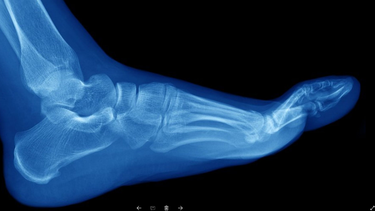

¿que son las fracturas de huesos por estres y quienes son mas propensos a sufrirlas?